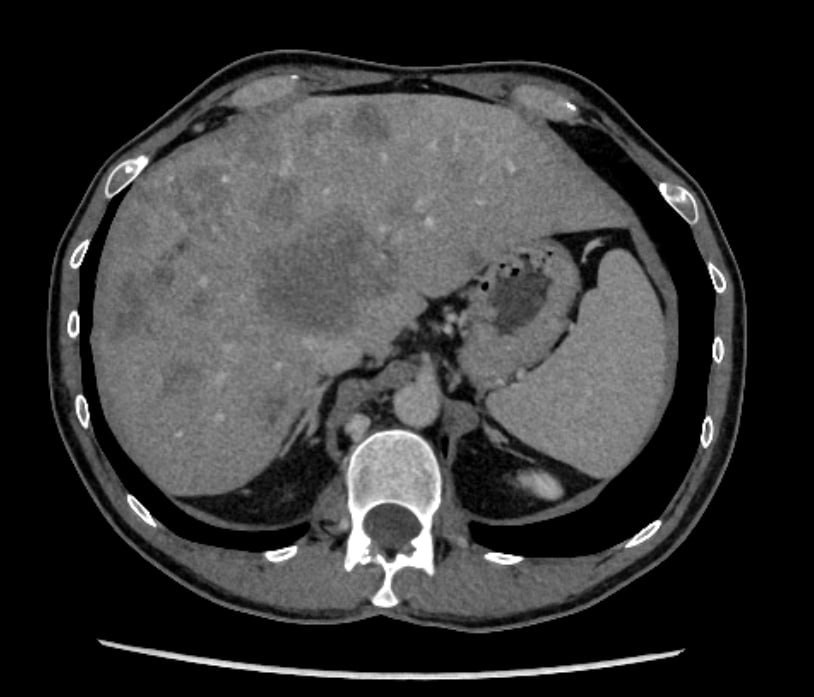

Here's an example of what a contrast-enhanced CT scan image looks like. This abdominal CT scan shows detailed internal structures that the contrast dye helps highlight:

This is a CT scan from Dima, OncoSteps' founder, showing extensive liver metastases from colorectal cancer after multiple rounds of chemotherapy. As someone who has personally navigated the challenges of cancer diagnosis and treatment, Dima founded OncoSteps to help others better understand their scans and make informed decisions about their care.